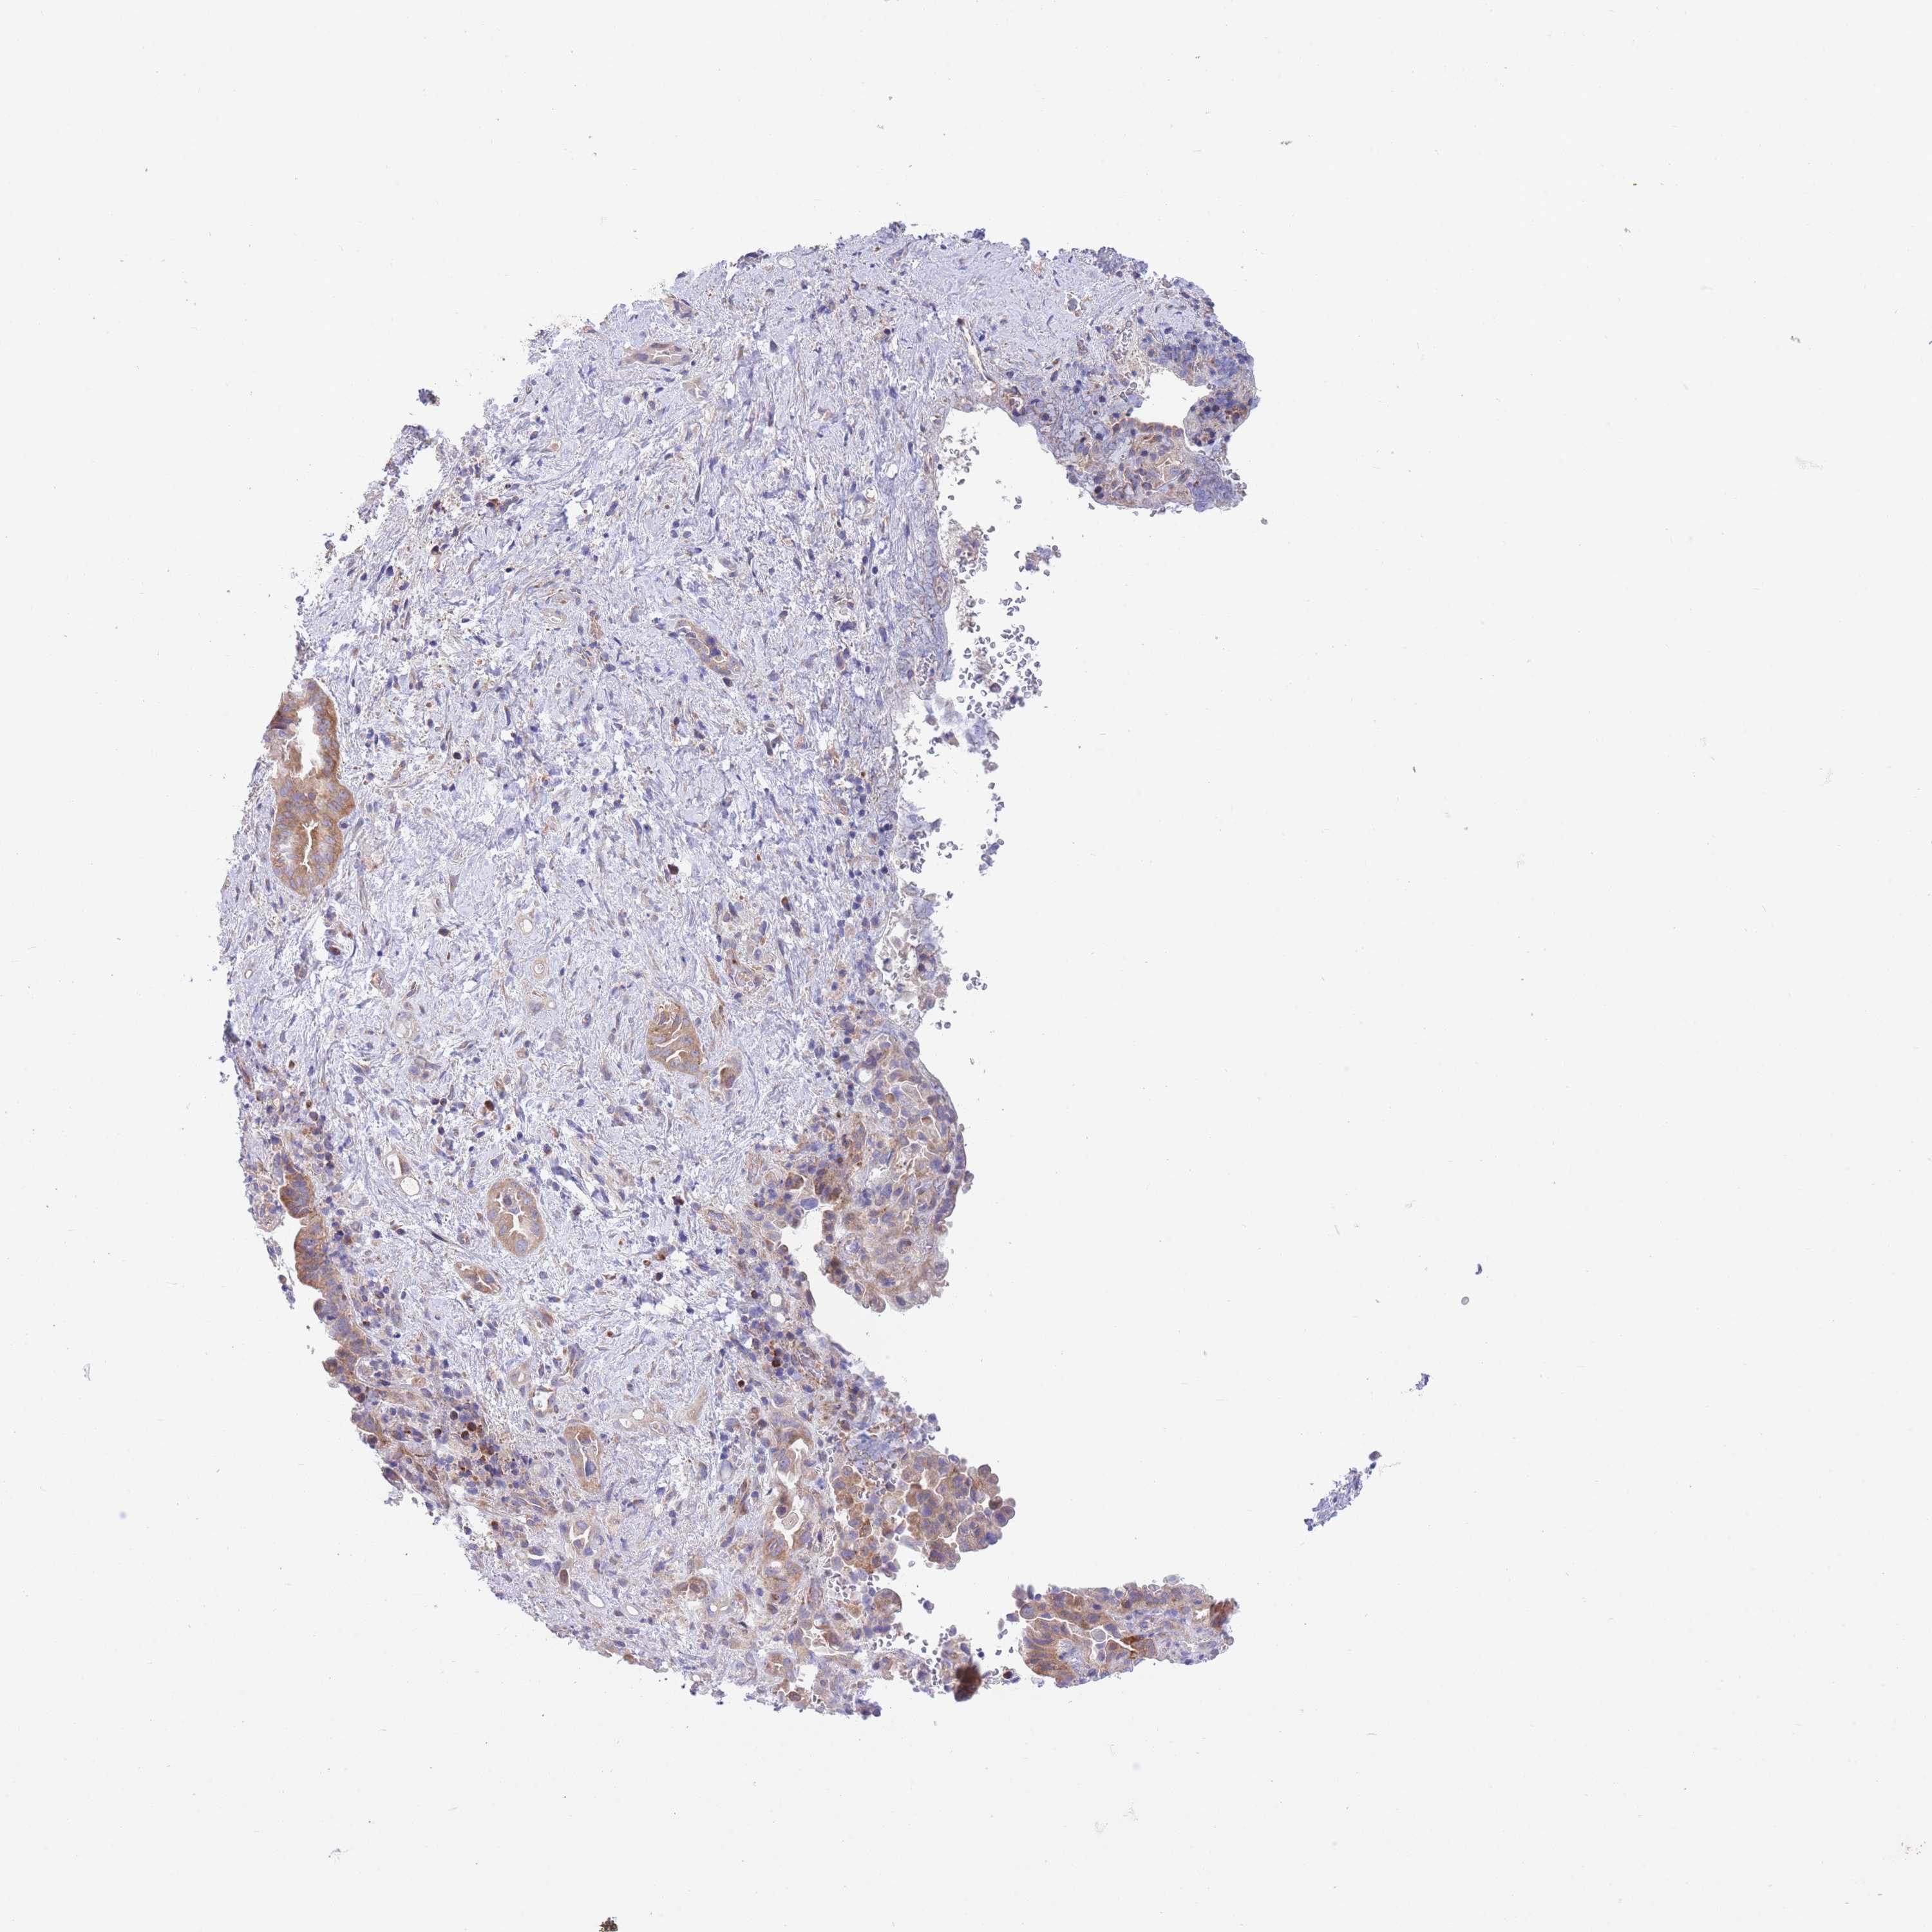

LIVER CANCER - Protein expressioni

A mouse-over function shows sample information and annotation data. Click on an image to view it in a full screen mode. Samples can be filtered based on level of antibody staining by selecting one or several of the following categories: high, medium, low and not detected. The assay and annotation is described here.

Note that samples used for immunohistochemistry by the Human Protein Atlas do not correspond to samples in the TCGA dataset.

Antibody stainingi

Antibody staining in the annotated cell types in the current human tissue is reported as not detected, low, medium, or high, based on conventional immunohistochemistry profiling in selected tissues. This score is based on the combination of the staining intensity and fraction of stained cells.

Each image is clickable and will lead to virtual microscopy that enables deeper exploration of all samples and also displays staining intensity scores, fraction scores and subcellular localization as well as patient and tissue information for each sample.

Antibody HPA042708

Antibody HPA043505

Staining

High

Medium

Low

Not detected

Intensity

Strong

Moderate

Weak

Negative

Quantity

>75%

75%-25%

<25%

None

Location

Nuclear

Cytoplasmic/membranous

Cytoplasmic/membranous,nuclear

Cholangiocarcinoma

Carcinoma, Hepatocellular, NOS